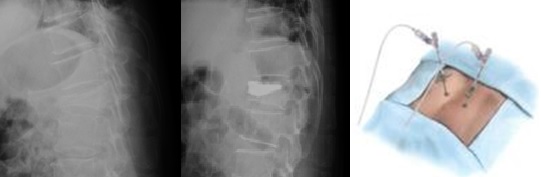

BKP(経皮的椎体形成術)とは

BKPは、体への負担が少ない先進的な治療法です。

つぶれてしまった椎体に5㎜程度の小さな傷から細い針を挿入し、その針先から風船を膨らませて骨の形を戻します。

その後、医療用のセメントを注入して固定する手術です。

手術は約30分程度の時間で終了します。